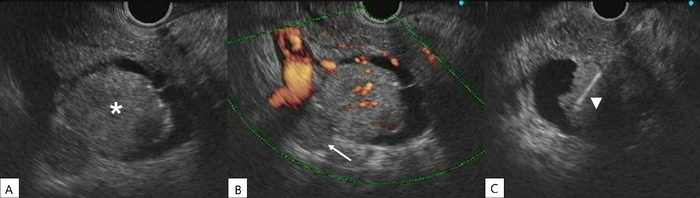

Case report: We report the case of a patient who developed a pancreatic metastasis from a classic variant papillary thyroid carcinoma 11 years after total thyroidectomy, cervical lymphadenectomy, and radioactive iodine ablation. The patient experienced increased thyroglobulin levels, and abdominal computed tomography scan revealed a lesion in the uncinate process of the pancreas. Tissue samples obtained by endoscopic ultrasound-guided biopsy were positive for thyroglobulin and thyroid transcription factor 1. Because the patient was not a candidate for surgery, the metastatic lesion was not iodine-avid, and tyrosine kinase inhibitors could not be offered because of tumor-related symptoms, the patient was treated with stereotactic body radiotherapy only. The patient died almost 2 years after the diagnosis of metastatic papillary thyroid carcinoma to the pancreas (13 years after total thyroidectomy for the primary cancer).